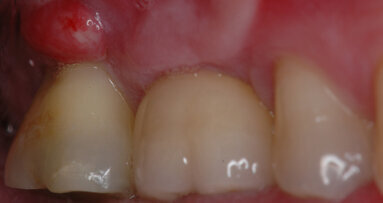

La paziente giunge in studio riferendo di aver avuto dolore spontaneo a carico del molare inferiore di sinistra e gonfiore della gengiva e che, dopo aver preso antibiotico e antidolorifico, ora avvertiva solo dolore alla masticazione e ancora infiammazione gengivale.

Clinicamente il dente risultava dolente alla percussione e presentava sondaggio puntiforme vestibolarmente (Figg. 1a- 1c). L’esame radiografico (Fig. 2) mostrava un’ampia lesione periradicolare.